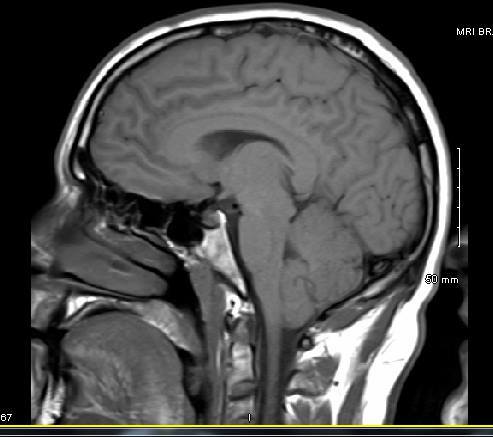

MRI anyone have any input? I go to the NS next week. Thanks!

No denying a herniation. Good luck with your appt. let us know what happens